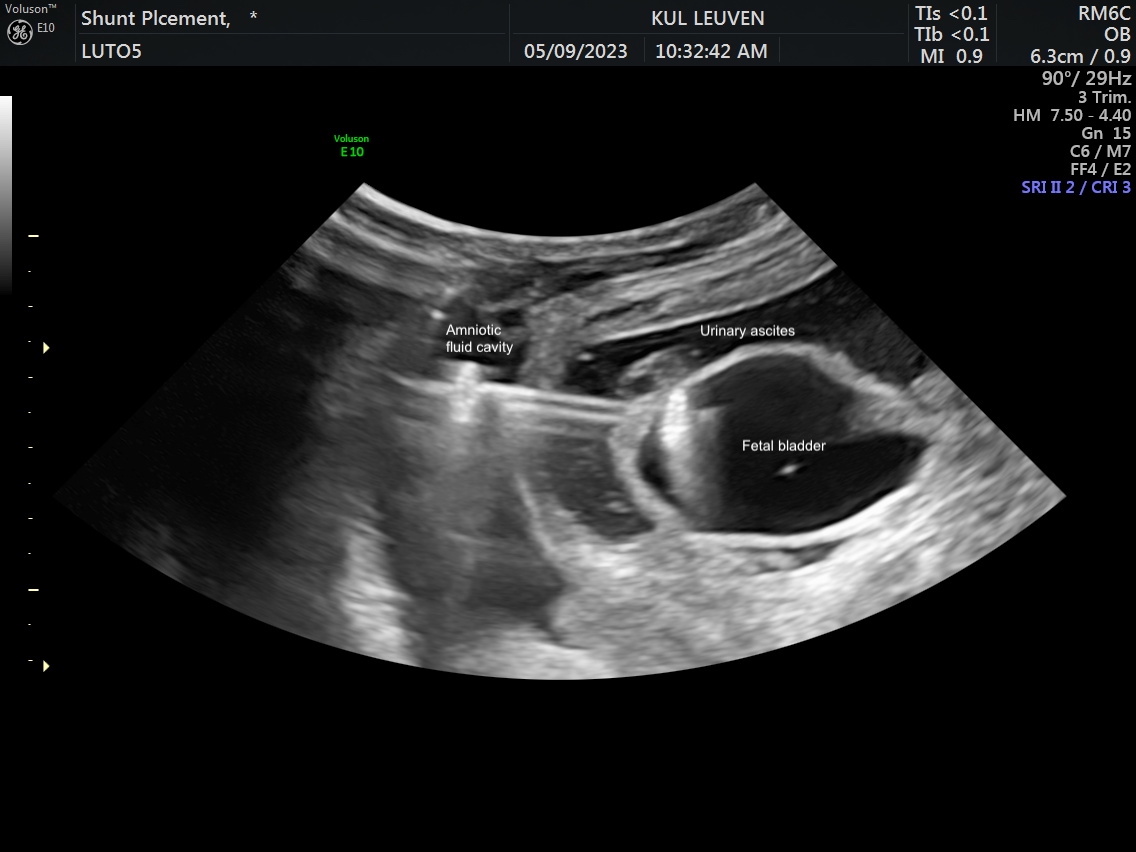

Methods: An acute pleural effusion model was developed by injecting saline into the fetal pleural space. Percutaneous thoracoamniotic shunt deployment was pursued in four fetuses at mid-gestation followed by immediate euthanasia and necropsy. The LUTO model was created in eight ewes at a median of 70 days (range, 69-72) gestation by ligating both the urethra and urachus. Severe LUTO with ultrasound features of megacystis, hydronephrosis, urinary ascites, and significant oligohydramnios/anhydramnios developed in 5 fetuses of which 4 survived. At a median of 98 days (range, 97-99), these 4 LUTO fetuses underwent Vortex shunt placement (2 non-valve shunts and 2 valve). Twenty-four hours post-deployment, shunt location was confirmed on fetal ultrasound and then on necropsy.

Results: All 4 thoracoamniotic shunt placements were successful placed with complete drainage into the amniotic space within minutes of deployment. For the 4 LUTO shunts, deployment was successful with the proximal anchor in the bladder and the distal anchor at the fetal abdominal wall within the amniotic sac (Figure 1). No dislodgement or kinking of the shunts were noted at 24 hours post-deployment on ultrasound with substantial improvement in oligohydramnios/anhydramnios. For the two non-valve shunts, the bladder was fully decompressed at 24 hours. For the two valve shunts, the bladder was partially decompressed at 24 hours with substantial decrease in bladder volume and urinary ascites. Correct shunt position was confirmed for all shunts on necropsy, and, all shunts were successfully removed through re-sheathing of the shunt. No damage to any surrounding organs was noted along the trajectory of the shunt deployment path (Figure 2).